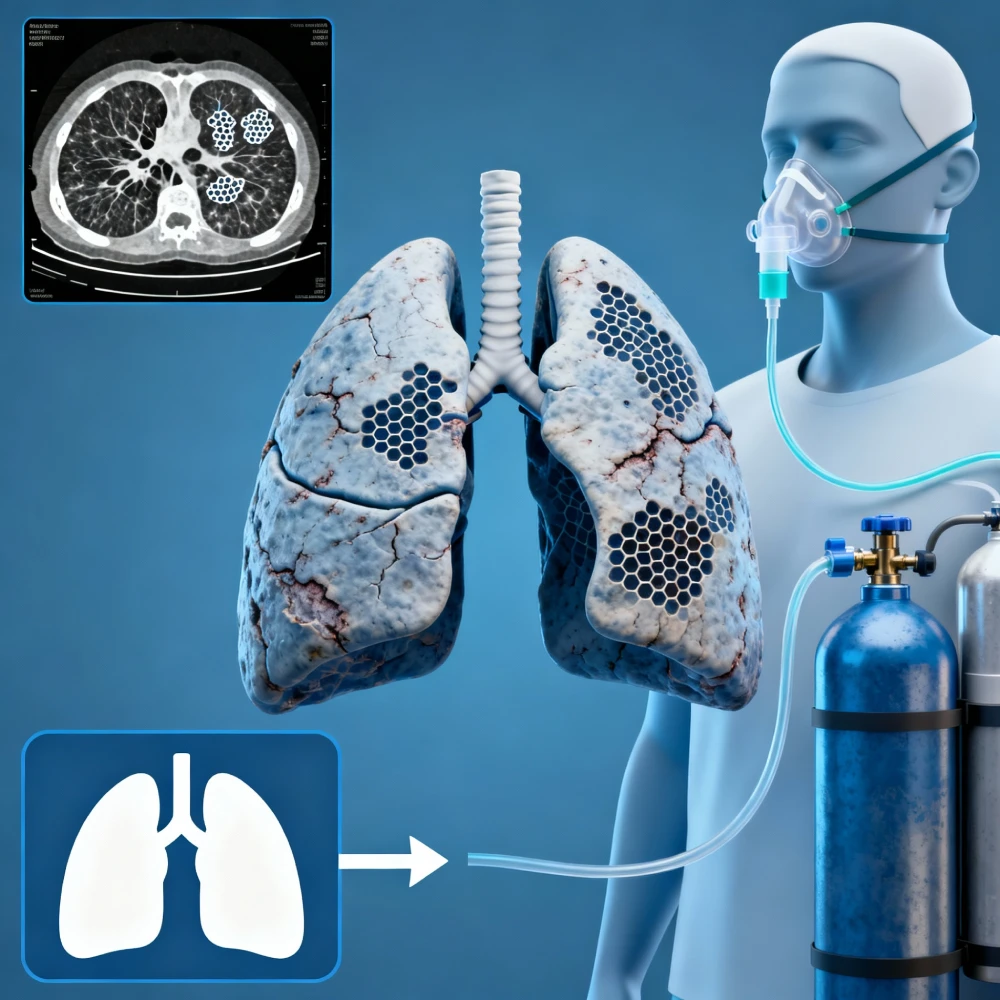

We have advanced care for Interstitial Lung Disease (ILD), which means you will get the best treatment for ILD, from lung scarring to providing precise diagnosis and management to protect your lung function. The lung specialist in our clinic utilises the latest methods for advanced lung testing to obtain a clear picture of your lung health, thereby guiding the most effective treatment.

We perform advance pulmonary function testing at our advance pulmonary care centre to measure how well your lungs are working, helping us understand your breathing capacity and identify issues. Our clinic also offers specialized TB care where TB specialists through complete diagnosis and treatment for tuberculosis focus on your full recovery.

With over 15 years of experience, Dr. Satyajit Acharya is dedicated to treating a wide range of lung conditions, from common coughs to complex conditions such as ILD and sleep apnea. He is highly trained, including advanced studies from CMC Vellore, and is known for giving clear, direct care. You can trust his deep knowledge and steady hands.

We offer everything you need for your lungs in one place. Whether it's advanced tests like bronchoscopy, detailed sleep studies, or managing conditions like severe asthma and TB, we handle it all. Our goal is to provide full, coordinated care so you don't have to go to different places for your treatment.

Our clinic uses the latest equipment for testing and treatment, like advanced pulmonary function tests and specialised scopes. This way we can get very accurate results quickly to make the right diagnosis. We also make sure to explain everything clearly, so you understand your health and treatment plan every step of the way.